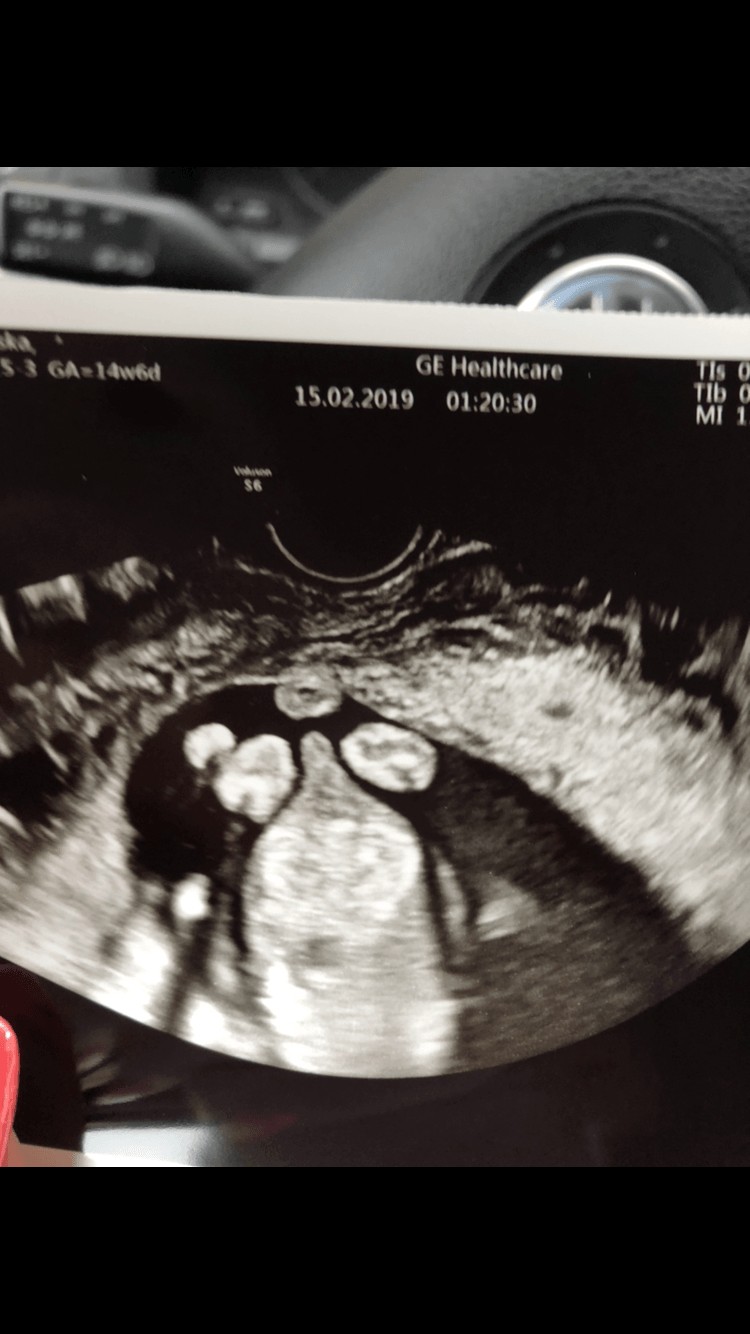

Usg chłopak czy dziewczynka

Witam w 19 tygodniu ciąży dowiedziałam się ze będę miała dziewczynkę w 20 tyg okazało się jednak , że to chłopak. Sama już nie wiem bo na jednym usg widać na pewno dziewuche a na drugim chłopca. Może to pempowina ?? Może ktoś mi pomoże rozwiązać ta zagadkę

Dziewczyny, czy to chłopak?;) lekarz powiedział ze obstawia chłopca, chociaż nie w 100%, bo nie widzieliśmy jajeczek, no i może to być pępowina....co sądzicie?;)